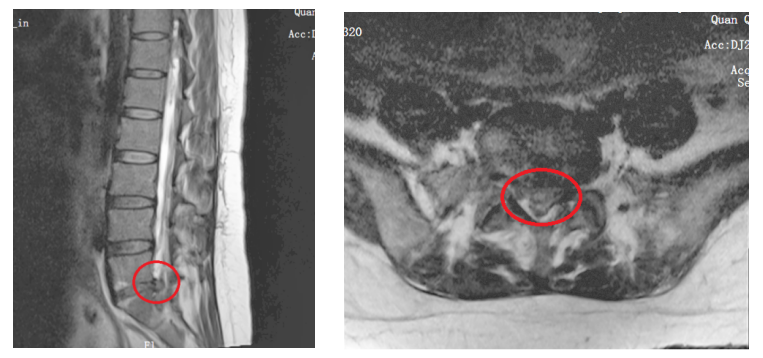

近日,河南省直第三人民医院脊柱微创外科由急诊120送来一位孕妇,一直喊着腰疼腿疼。原来王女士(化名)深受腰椎间盘突出的折磨,已经在床上躺了半个多月,天天腰腿疼的睡不着觉。王女士在怀孕4个月时,腿部感觉稍微有点疼,以为是孕期缺钙,就没在意。半个月前一个早上,突然腿疼加重,去医院检查发现,腰椎退行性改变,腰5-骶1椎间盘脱出。当地镇上医生建议先静养,虽说休息了一段时间稍微有所减轻,但腿疼的还是不能站、不能走,也不能坐,只能躺着,即便是躺在床上腿也是抽筋一样的疼,疼的日夜难眠,并且出现了大小便异常的情况。

看着王女士痛苦的样子,老公带着她去了当地县医院。医生说现在孕妇已经出现了会阴部麻木、大便异常的马尾神经症状,需要尽快手术,建议先打掉孩子再手术。对这个家庭来说,这是他们的第一个孩子,自然是万分不舍。王女士和家人坚持要保住孩子,当然病也要治。经多方打听,了解了河南省直第三人民医院治疗腰椎间盘突出很有名气,她和家人决定试试看。于是在当地医院的帮助下,紧急送至郑州。王女士入院后经过相关检查,发现胎儿一切正常,在妈妈的腹中健康成长,此时还没有受到牵连。但是孕妈妈合并腰椎间盘突出,突出的椎间盘长期压迫神经根会引起神经根不可逆损伤,出现下肢肌力下降,肌肉萎缩,大小便费力或失禁等并发症。再加上孕妈妈长期处于疼痛状态,还可能引发胎儿早产等情况。手术势在必行,但是为孕妇做手术,难度极大,风险重重。该如何治疗,既能驱除病痛又减少对胎儿的影响呢?常规来说,全可视脊柱内镜治疗王女士的椎间盘脱出完全没问题,但是,术前评估及术中定位操作时不可避免的高剂量的射线暴露,可能会对胎儿产生不利影响。

脊柱微创外科二病区主任马海军立刻组织医院妇产科、麻醉手术部及超声科共同会诊,科室的各位专家从专业角度为治疗方案出谋划策。在医院相关科室的共同努力下,马海军主任带领团队给予彩超下定位,局部麻醉,在零透视的情况下,行全可视脊柱内镜微创手术,对胎儿没有任何影响,手术顺利完成。

突出的髓核(罪魁祸首)

在手术室门口等待的老公,看见媳妇从手术室里走出来非常激动。“现在一点也不疼了,你看,没事儿了,我可以走路了。”王女士抱着老公激动地说,“终于可以正常走路,睡个安稳觉了”。术后休息几天后,王女士安心回家休养,等待着新生命的降临。据马海军主任介绍,利用超声术前定位,找到脊柱间隙,通过掌握的脊柱外科专业解剖结构知识和脊柱内镜的熟练操作技术,在镜下一步一步从皮下到椎板,整个结构完全充分的暴露出来,打开黄韧带,看到了整个脱出游离的椎间盘组织,对神经根硬膜囊达到一个充分减压,精准定位,避免射线对孩子的影响,保证了孩子的安全,同时也解决患者的病痛。目前,孕妇合并椎间盘突出症的概率较高,正常人椎间盘突出症发病率约10%至20%,孕妇的发病率更高,但也不是每个人都有症状。孕妇高发的主要原因是在怀孕期间整个腰部肌肉、韧带系统处于松弛状态,随着孕周的增大,腰骶部承受的重量比平时更加大,这就增加了腰椎间盘突出的风险。另外,孕期弯腰或者做其他动作时,腰骶部的压力也会比平时更大,进而加重椎间盘突出。马主任建议,在怀孕之前已经有椎间盘突出症状的女性,应进一步检查明确诊断,进行保守治疗或外科手术治疗,恢复到正常状况后再怀孕,避免孕期加重腰椎间盘突出。如果孕期出现腰腿痛,在专科医生指导下,可先进行卧床休息、热敷、理疗等保守治疗。如果保守治疗效果不理想,严重影响生活质量,经过多学科专家综合评估后,再进行手术治疗。